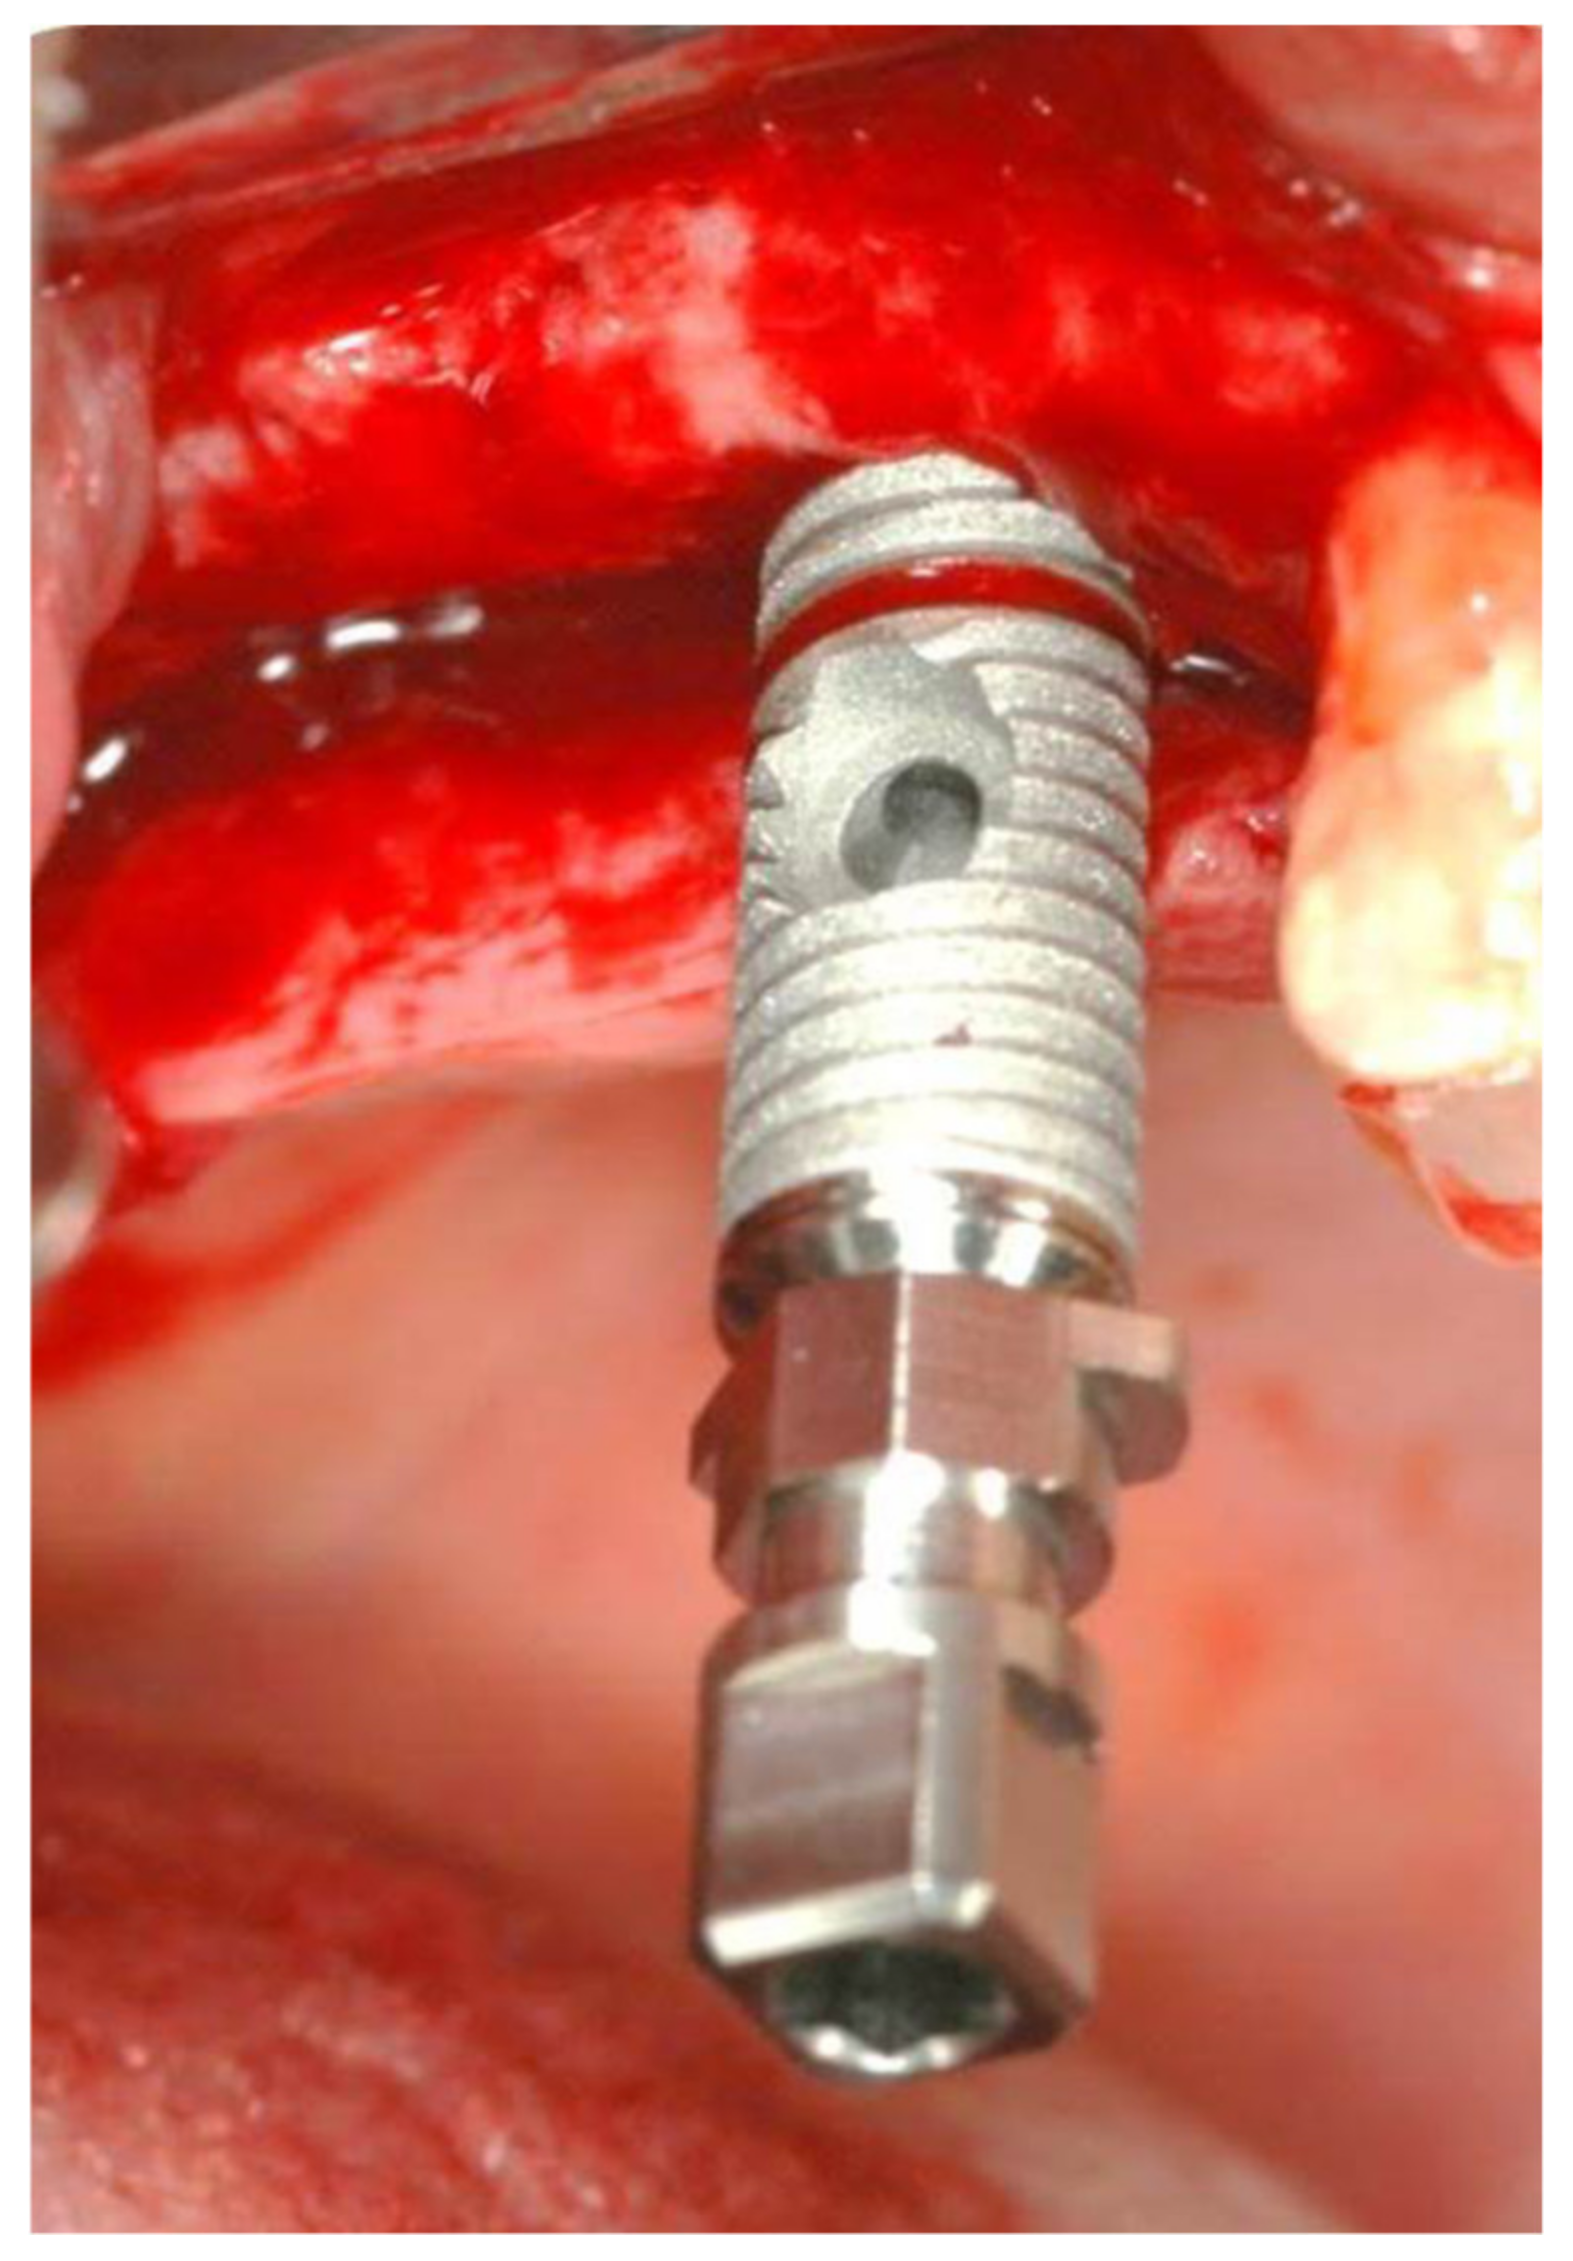

2.1. Standard Surgical Procedure